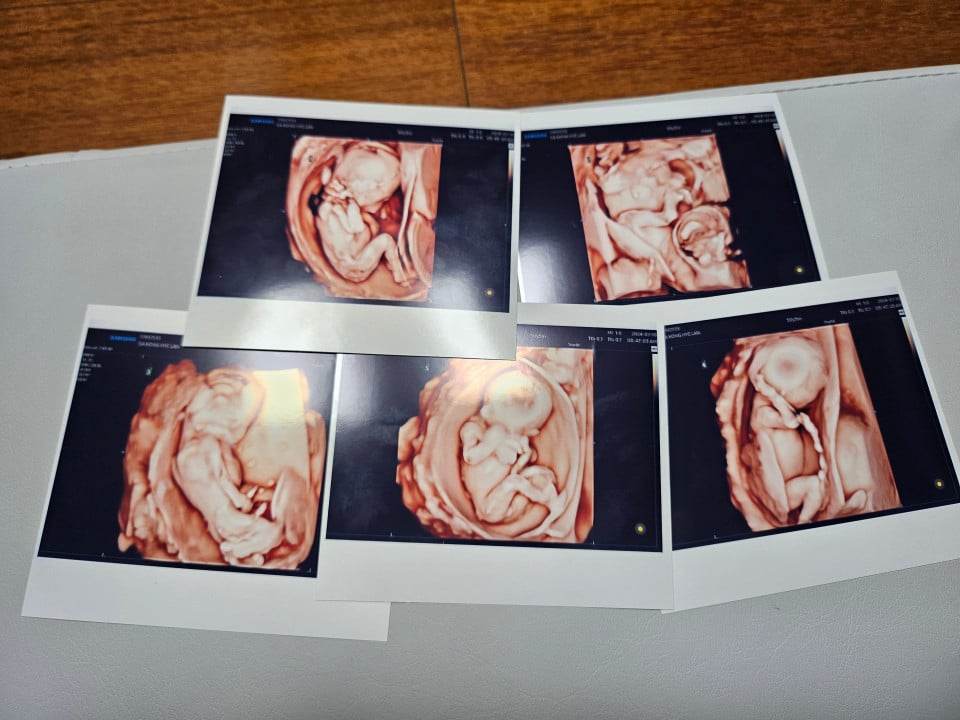

20 Eylül'de dünyaya gelen üç erkek ve iki kız bebek, ülkenin ilk doğal beşiz doğumu olarak kaydedildi.

Sezaryenle dünyaya gelen bebekler ülkenin hızla düşen doğum oranlarıyla mücadele ettiği bir dönemde cesaretlendirici bir örnek olarak yorumlandı.